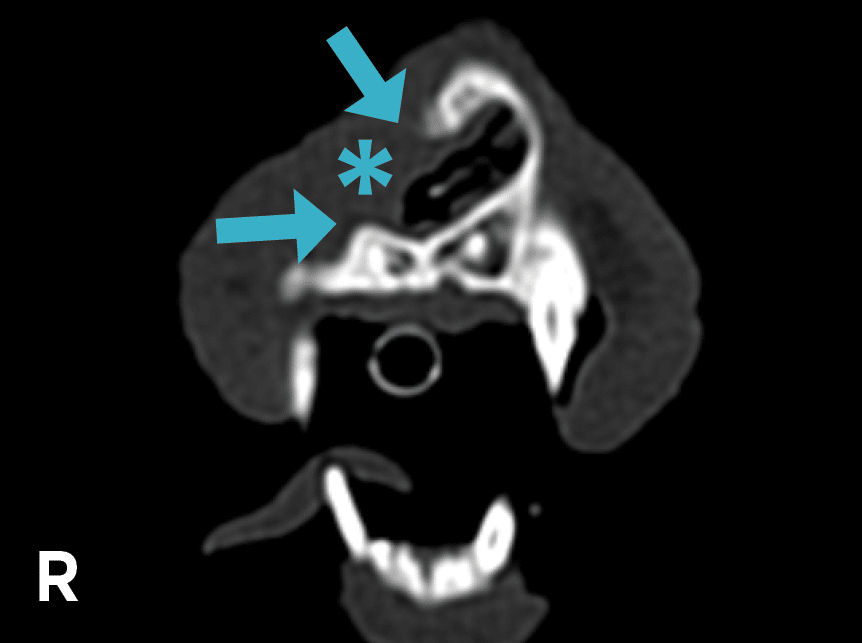

On CT, defects in the right nasal and incisive bones were noted (FIGURE 3), and the entrance to the right nasal cavity was obstructed with soft tissue. The nasal septum was deviated, with a right ventral to left dorsal orientation. Caudal to the canine tooth roots, the right nasal cavity was smaller than the left, and there was asymmetry of the nasal turbinates. Aberrant turbinates were noted within the right side of the choana.

Figure 3. Nasal obstruction by soft tissue (asterisk) and bone loss (arrows) evident on computed tomography.